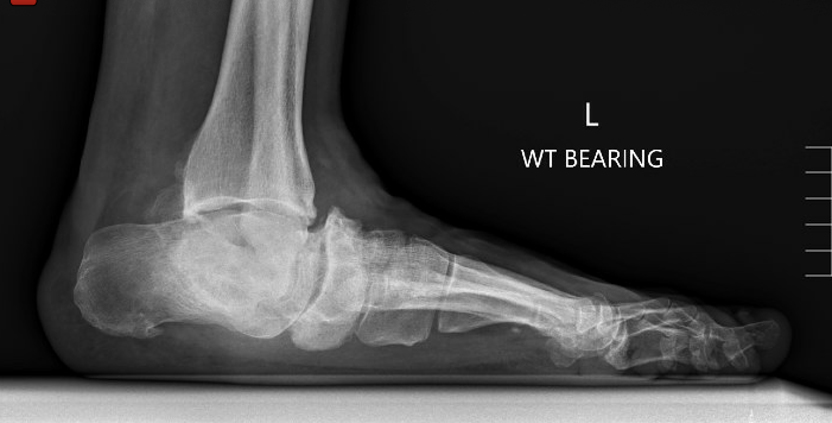

TOTAL ANKLE REPLACEMENT :: ORIF CALCANEUS :: ORIF ANKLE FRACTURE DISLOCATION :: COMPLEX BUNION AND LESSER TOE CORRECTION :: TALUS FRACTURE -1 :: TALUS FRACTURE -2 :: LISFRANC REPAIR :: COMPLEX TRIPLE ARTHRODESIS 1 :: COMPLEX TRIPLE ARTHRODESIS 2 :: MINIMALLY INVASIVE BUNION REPAIR 1 :: MINIMALLY INVASIVE BUNION REPAIR 2 :: ARTHROSCOPIC CARTILAGE REPAIR :: TENEX SPUR DEBRIDEMENT :: Haglunds Debridement and Achilles Repair